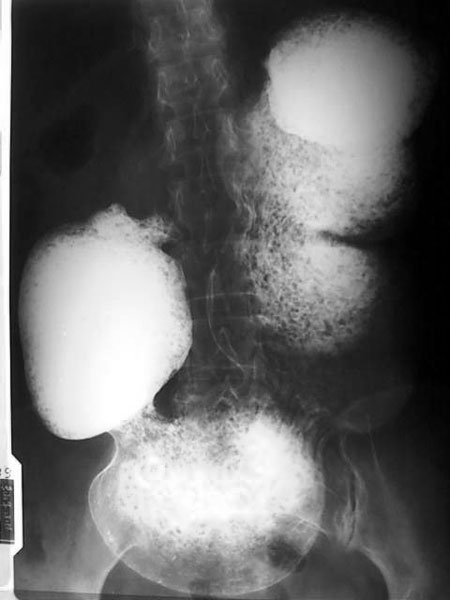

女,45岁,腹胀、腹痛不适数年,未扪及腹部包块。

胃下垂是肯定的,至于十二指肠球部有无问题则不好说,所给片子不全面!

胃的蠕动正常,好象不是低张造影!不是低张造影,胃的体积却这么大,为什么?感觉象是胃扩张,但不是急性的!胃的张力和蠕动正常,只是体积增大,我不支持胃下垂的诊断!!是什么,确实没有见过,静侯各位老师分析.....

支持胃下垂伴胃内大量潴留液,但要除外胃出口梗阻。

胃下垂伴胃内大量潴留液,小肠内无造影剂,提示幽门或十二直肠梗阻。

我认为胃下垂的诊断不应该只是一个胃大弯下界的位置改变,更重要的是胃张力和蠕动的改变.日常工作中瘦长体形的人胃的下界也很低,甚至底于髂骨上缘连线下5厘米,但是胃的排空和张力正常,并没有任何下垂症状,这样的患者我们如何能诊断为胃下垂??

胃下垂伴胃内大量潴留液,十二指肠球部似有变形,不除外球部溃疡所致!

胃腔扩大,内有潴留物,12指肠未见确切显影。胃扩张,考虑幽门或十二指肠梗阻。

胃下垂伴胃内大量潴留液,胃腔内小结节样低密度影,可能为服下的小颗粒状产气粉附着在潴留物上所致,小肠内无造影剂,提示幽门或十二直肠梗阻。